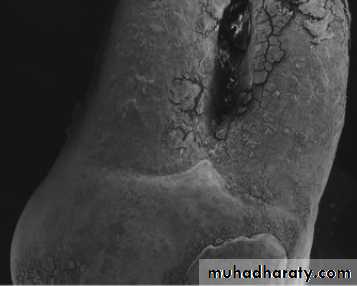

Enamel Pearls

• The anatomy of the furcation is complex, The presence of bifurcational ridges, a concavity in the dome, and possible accessory canals, Cervical Enamel Projections, Enamel Pearls complicates not only scaling, root planing, and surgical therapy, but also periodontal maintenance.Cervical Enamel Projections